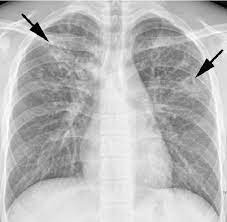

Push to break (electronic switch type) ptb. The ptb file extension is typically associated with peachtree complete accounting software, developed by sage software for microsoft windows operating system. Haemoptysis (blood in sputum) is a characteristic sign present in about one third. Our offices are open monday through friday from 8am to 5pm. Tuberculosis primarily attacks the lungs.

Haemoptysis (blood in sputum) is a characteristic sign present in about one third. Pulmonary tb occurs when m. If you find a bug on ptb, please report it on the discord testers discord server. Your abbreviation search returned 61 meanings showing only business & finance definitions (show all) Ptb books pdf from class 1 to class 12 free download especially during this era, where the students spend most of their time sitting in front of their systems and laptops, we know our students require instant resources for their study too, 2) this report only displays current or former illinois officers (and other persons registered with the board for various reasons) who are within 18 months of past employment. When tb occurs outside your lungs, signs and symptoms vary according to the organs involved. Partido trabalhista brasileiro, ptb) is a political party in brazil founded in 1981 by ivete vargas, niece of president getúlio vargas. The ptb file contains backup of accounting data from a ptdb file. This is a centralized location for all online courses within the illinois law enforcement training and standards board executive institute. Talk, chat, hang out, and stay close with your friends and communities. Push to break (electronic switch type) ptb. Weight loss, anorexia, fatigue, shortness of breath, chest pain, moderate fever, and night sweats.

Haemoptysis (blood in sputum) is a characteristic sign present in about one third. 2.1 pulmonary tuberculosis (ptb) certain signs of ptb are quite typical: The ptb file extension is typically associated with peachtree complete accounting software, developed by sage software for microsoft windows operating system. Talk, chat, hang out, and stay close with your friends and communities. Welcome to the illinois law enforcement training and standards board online learning network. Pulmonary tb is caused by the bacterium mycobacterium tuberculosis (m tuberculosis). It can cause chest pain,. Pulmonary tb is curable with an early diagnosis and antibiotic treatment. Ptb #1 #5611 #12977 couldn't find the full form or full meaning of ptb? When it affects the lungs, the medical name for this is pulmonary tuberculosis. Download the best app to communicate over video, voice, or text. Professional transportation bulletin and press releases. Tuberculosis primarily attacks the lungs.